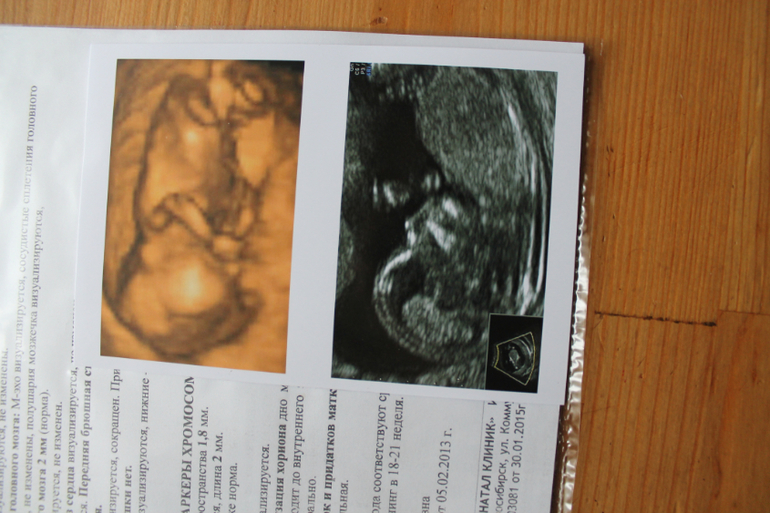

сходила на узи все отлично не каких отклонений (фото ребеночка ниже)

УЗИ, КТГ, доплерСказали будем надеяться на девочку ))))) Узистка оказалась очень приятной все показала рассказала я очень довольна!!!